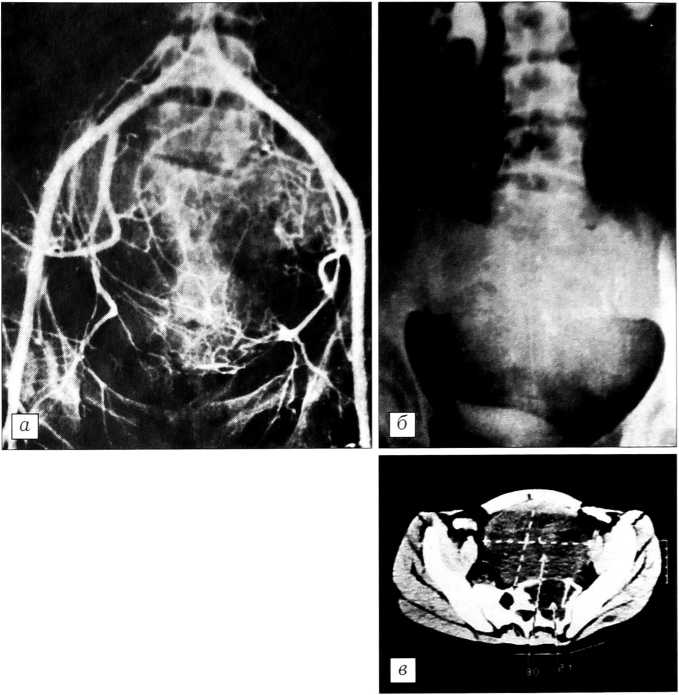

Рис. 4. Больная Б 28 лет. Диагноз: злокачественная гигантоклеточная опухоль (?), компрессионный спинальный синдром (парез левой руки). На рентгенограмме (а) разрушение тела и дуги С2. Выполнена одномоментная спондилэктомия, дефект спереди заполнен аутотрансплантатом от основания черепа до С4, сзади — окципитоспондилодез аллотрансплантатом (б). Гистологическое исследование: остеобластокластома с атипизмом клеток.

При локализации опухоли в боковой массе атланта в одном случае мы применили переднебоковой доступ с временным отделением кивательной мышцы от сосцевидного отростка по методике F. Bongioanni и соавт. [36]. При литических опухолях в теле С2 (миелома, злокачественная ГКО, лимфома) рекомендуем двухэтапное лечение. Первый этап — наложение гало-аппарата без вмешательства на очаге поражения, для воздействия на очаг может быть проведена химио- или лучевая терапия. Второй этап — операция из переднего доступа в аппарате — спондилэктомия + костная пластика; при необходимости можно выполнить и окципитоспондилодез, также в аппарате (рис. 5). Для дальнейшего лечения больной переводится в онкологическое учреждение. Аппарат снимается после образования костного блока (4 мес). При локализации опухоли на уровне С3-7 показан передний доступ. Удаление опухоли следует производить единым блоком вместе с дисками и смежными замыкательными пластинками. При показаниях можно удалить два или три позвонка вместе с дисками. Дефект мы обычно заполняем аутотрансплантатом, он должен быть плотно внедрен в подготовленное ложе и дополнительно фиксирован трансоссально.

Рис. 5. Больная О. 42 лет. Диагноз: миелома со сдавлением спинного мозга. На рентгенограмме (а) разрушение С2 позвонка с деформацией верхнешейного отдела. Оперирована в два этапа: 1) наложение гало-аппарата, устранение деформации + химиотерапия; 2) окципитоспондилодез пластинами из титана (б) + химиотерапия.